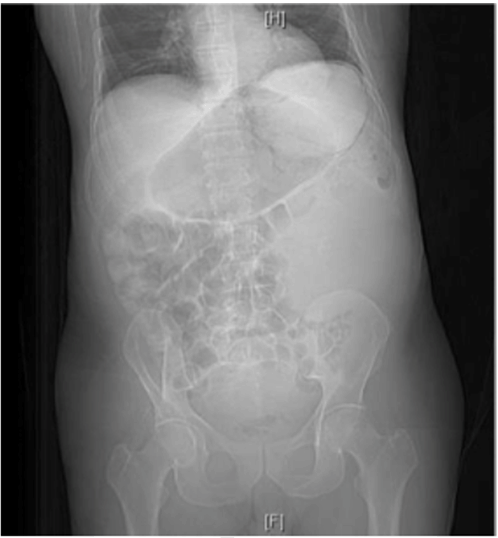

A 60-year-old male with disabling paranoid schizophrenia was sent from his group home to the emergency room after an unwitnessed fall and sustaining a left tibial-fibula comminuted fracture. The patient was admitted to the hospital for medical optimization of his poorly controlled diabetes and hypertension in anticipation of surgical repair. However prior to any intervention, he developed an acute onset of non-bilious emesis and abdominal distention. The patient reported previous such episodes which resolved without any intervention. He denied any abdominal surgery, family history was unknown and his recent screening colonoscopy was normal. On exam, his abdomen was soft, markedly distended but there was no evidence of peritonitis. He was afebrile and hemodynamically stable. His laboratory values were all within normal limits, without evidence of a leukocytosis or acidosis. A bedside abdominal X-ray showed a distended stomach with a paucity of gas in the small bowel and large fecal burden in the colon (Figure 1). In the absence of any previous abdominal surgery, a computed tomography (CT) scan with only oral contrast was obtained. It revealed a 17-cm pedunculated mass compressing the gastric antrum causing marked dilation, however, there was no evidence of pneumatosis. A nasogastric tube was placed for decompression, and the patient obtained a CT scan with oral and intravenous contrast to ascertain the etiology of this mass. This subsequent CT scan revealed the known heterogeneously enhancing solid mass with eccentric calcification with pedicle inseparable from the duodenum/gastric pylorus. However, there was an interval migration of the mass from the right abdomen to the left with possible twisting on the mesentery (Figure 2). There was new gastric pneumatosis as well as new portal venous gas. The decision was made to emergently take the patient to the operating room for an exploratory laparotomy. In the operating room, a midline incision was made to enter the peritoneal cavity and immediately a large well circumscribed mass was visualized in the left lower quadrant. The mass was pedunculated and the broad base originated from the inferior aspect of the liver arising from the lesser omentum. This mobile base draped over the gastric antrum and first part of the duodenum causing the mechanical gastric outlet obstruction (Figure 3). On further exploration, there was no evidence of ascites, lymphadenopathy, or any distal metastasis. The anterior and posterior serosal surfaces of the stomach were carefully inspected and showed no signs of ischemia. The pedicle was suture ligated and divided at the origin and the specimen freely delivered from surrounding structures. This was sent to a regional tertiary referral oncology pathology unit. On gross report the tumor measured 17x15x10.5 cm and weighed 1.5 kg. It was described as having a rubbery to fleshy cut surface and focal cystic areas (Figure 4). Microscopically, the findings were that of a spindle cell sarcoma with large areas of necrosis as well as increased mitotic activity 8-10 MF/10 HPFs. Although the tumor was mostly composed of a monotonous proliferation of spindle cells separated by a prominent fibrous and sclerotic stroma, there were scattered pleomorphic cells throughout. The immunohistochemical stains show the tumor was diffusely positive for CD34, while negative for CD 117, S100, smooth muscle actin (SMA), CD31 and Factor VIII. Based on the clinical presentation, histologic appearance of a spindle cell lesion associated with abundant collagenous stroma and CD34 reactivity, one possibility included a malignant solitary fibrous tumor. In order to confirm this diagnosis further immunostaining for a recurrent gene fusion NAB2-STAT6 was found to be positive, confirming the diagnosis of SFT. The patient was observed and his postoperative course was uneventful. His NGT removed on postoperative day-1. The patient was discharged after he tolerated a regular diet with return of normal bowel function on postoperative day-2. On immediate postoperative and a three-month follow-up visits, he has been without any recurrence of symptoms.

Figure 1: Abdominal X-ray showing markedly dilated stomach.